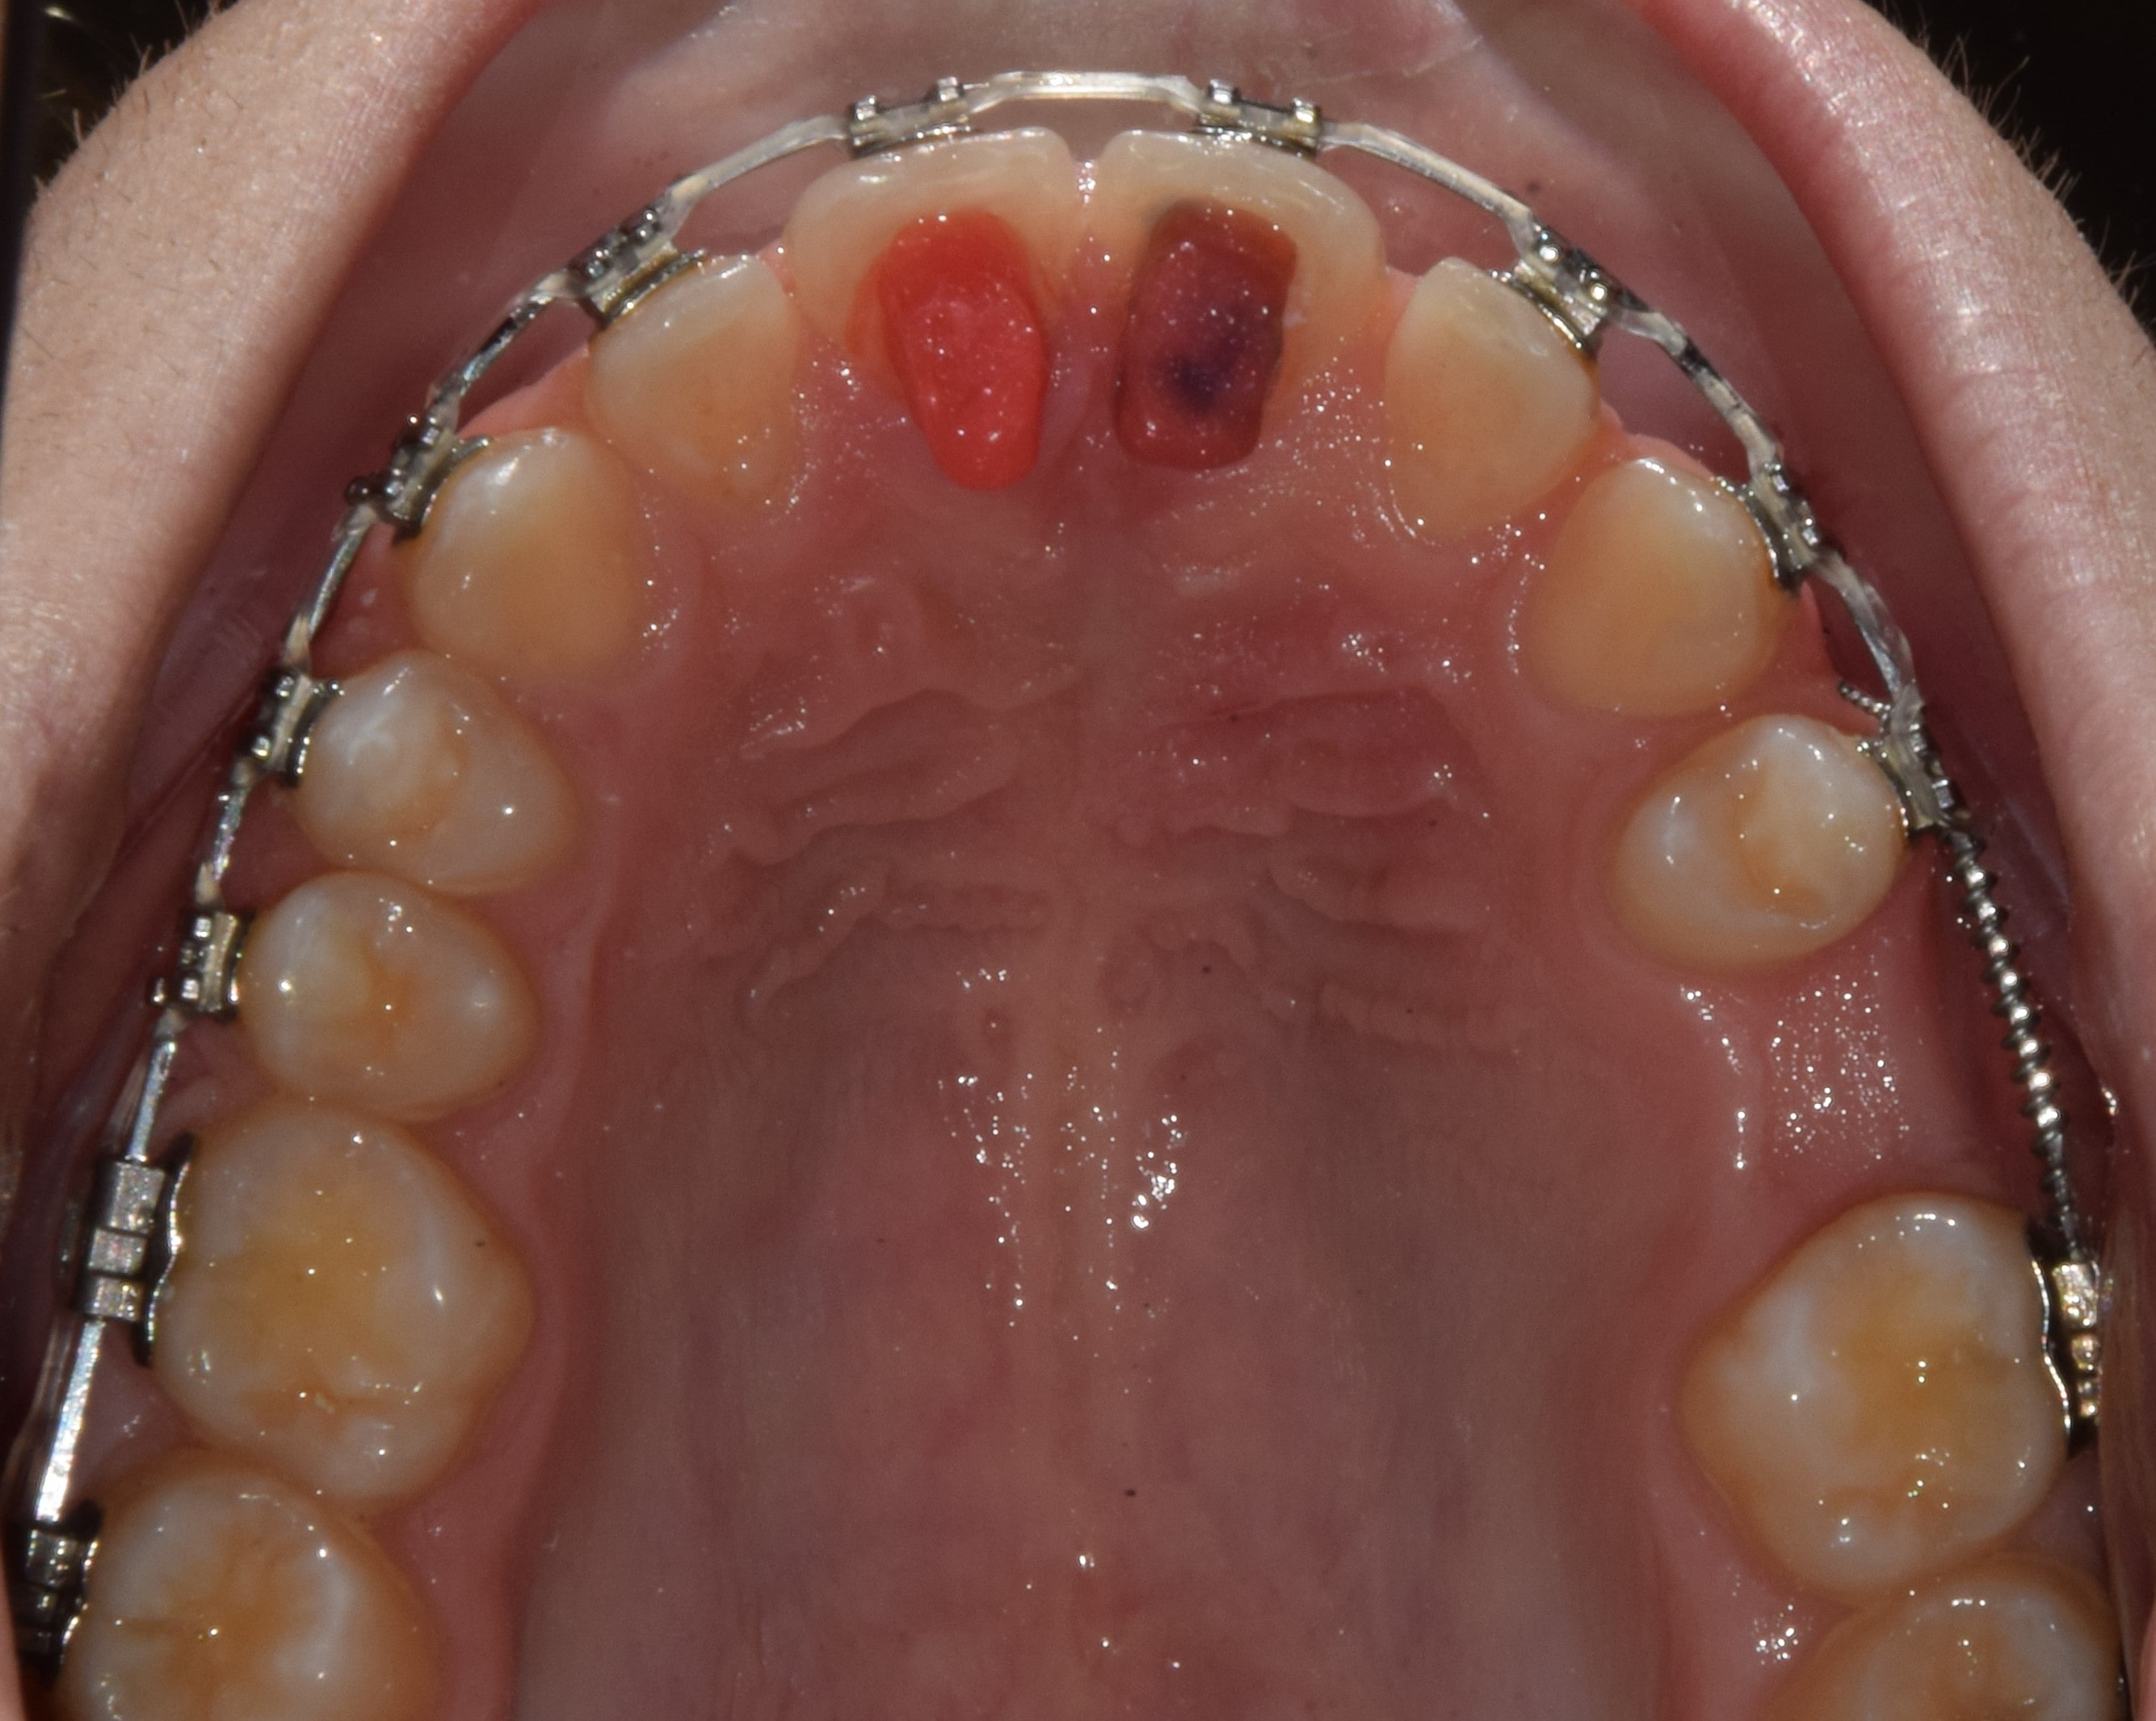

Számfeletti fog

Amennyiben a normálistól eltérően több fog található a szájüregben, úgy számfeletti fogakról beszélhetünk. Ezek lehetnek valamely maradó foggal megegyező formájúak (dens supplementarius), vagy teljesen random alakúak (dens supernumerarius). Eltávolításuk javasolt, amennyiben befolyásolhatják az egészséges fogakat, azok előtörését, épségét. Ha nagy számú számfeletti fog látható, érdemes gyanakodni valamilyen általános megbetegedésre, szindrómára.